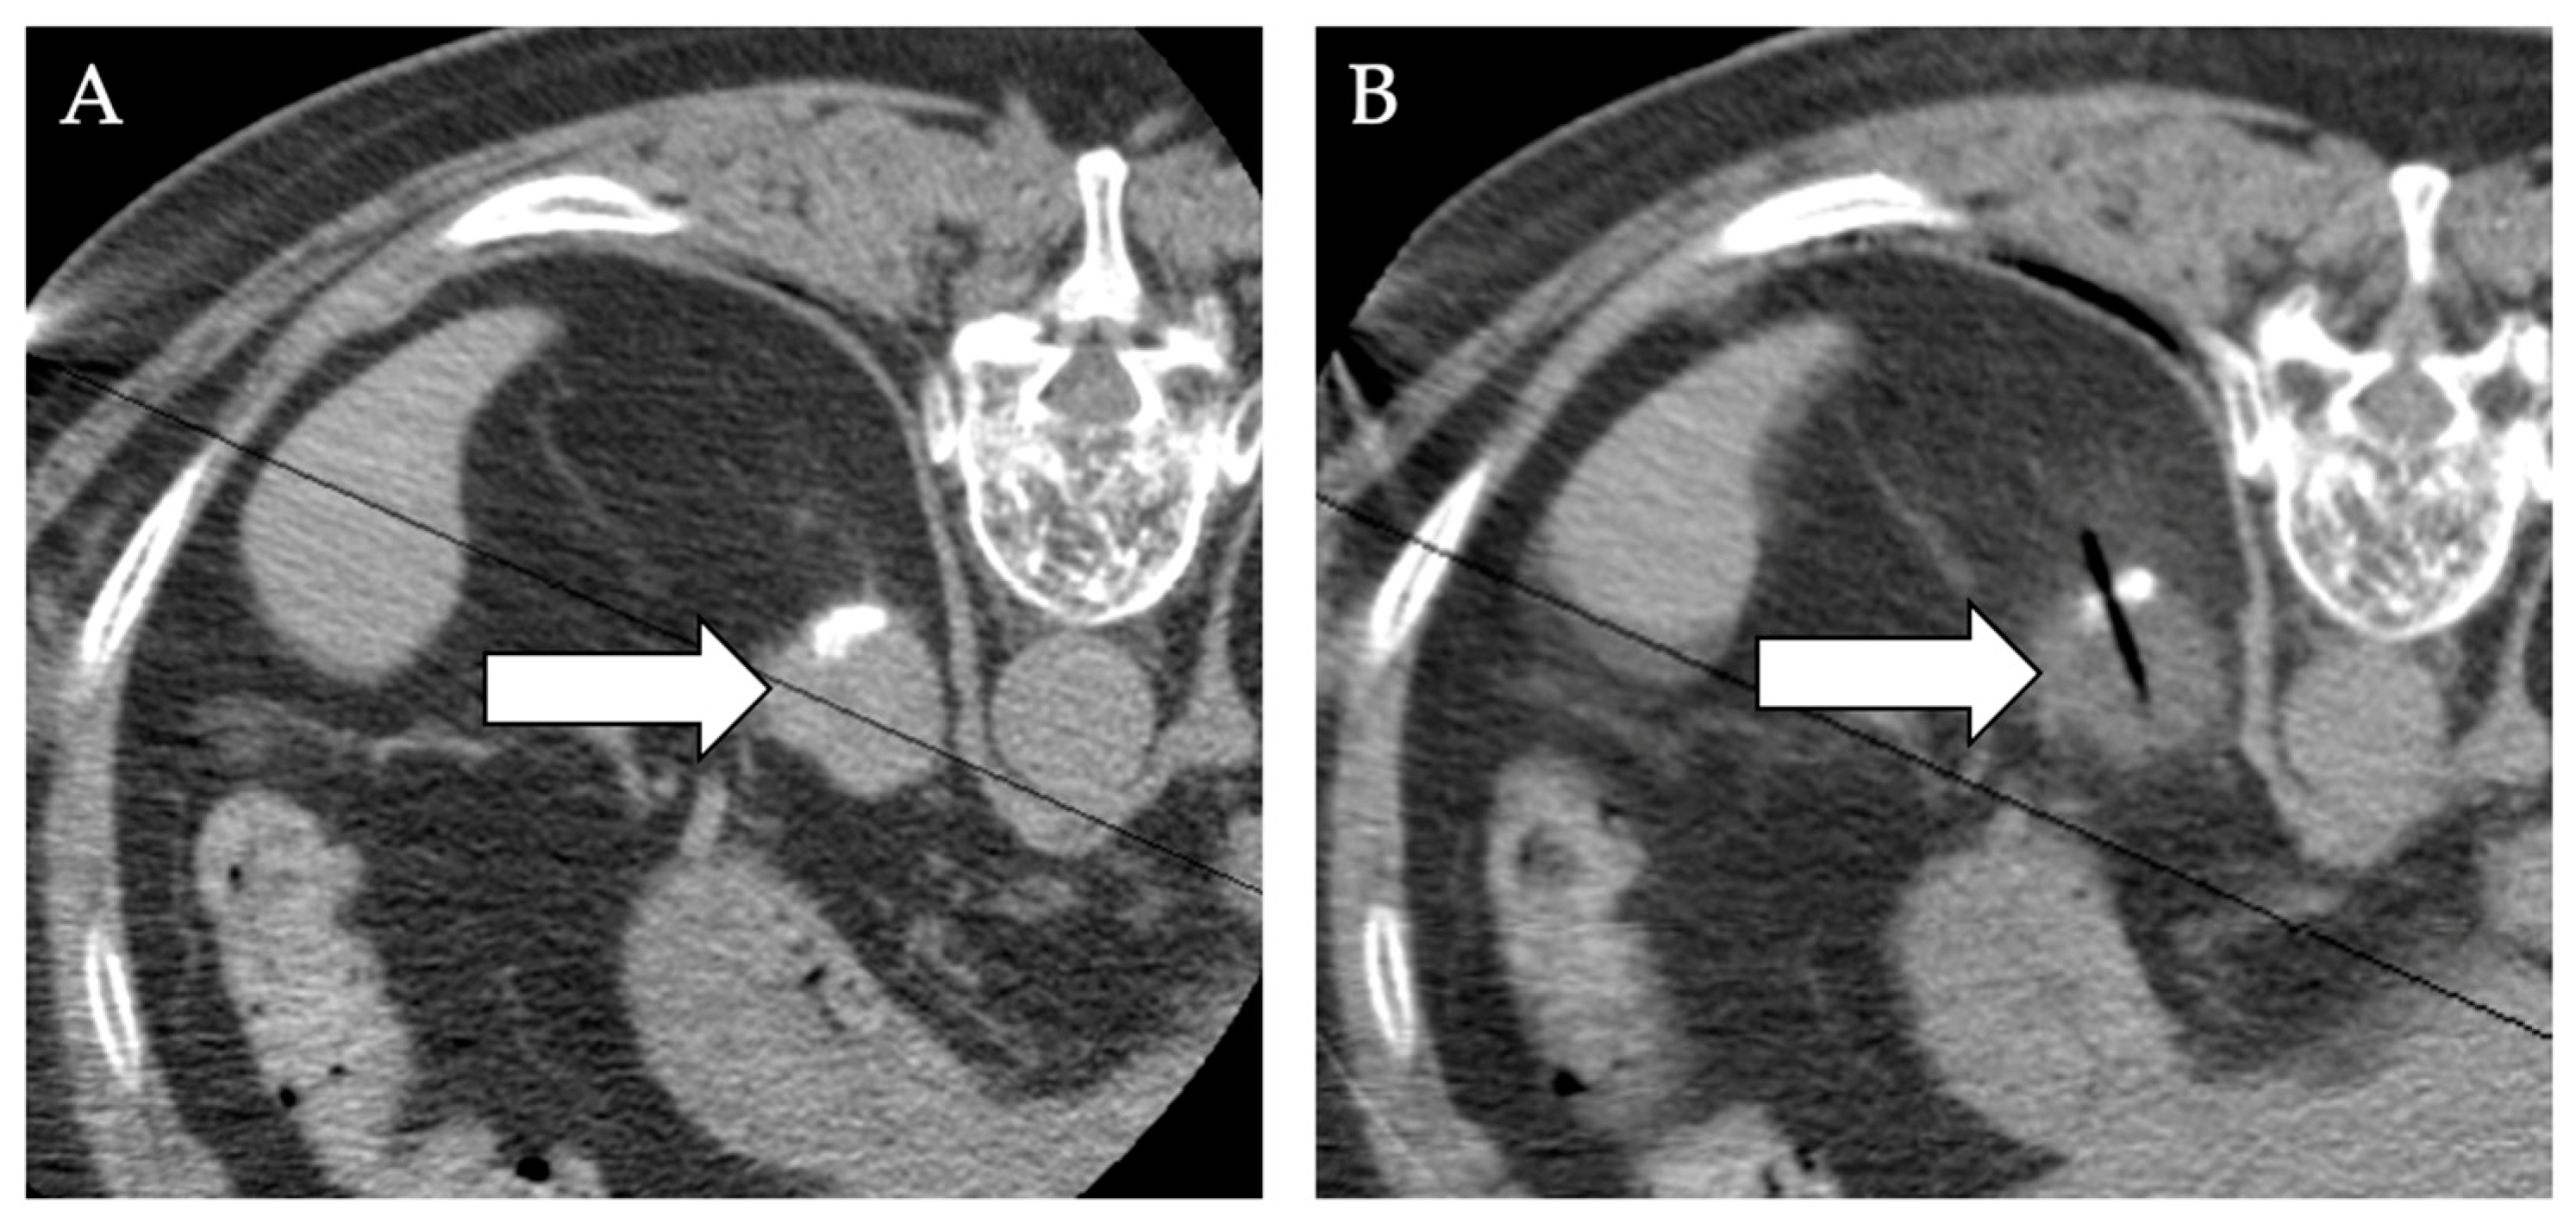

7. Primary and Metastatic Adrenal Tumors